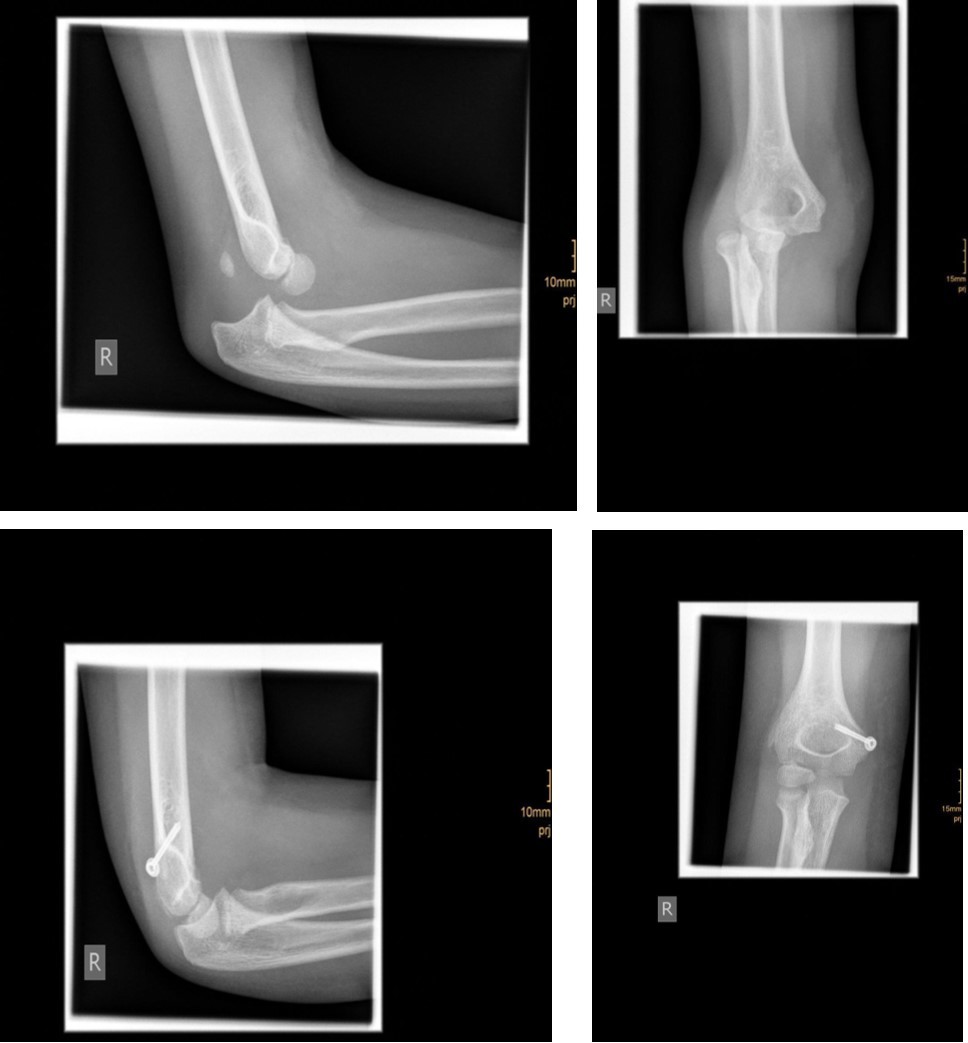

The degree of displacement may be seen on the true lateral view. In determining whether the articular hinge is intact (i.e., stage I vs. stage II), the relationship of the proximal ulna to the distal humerus is evaluated for the presence of lateral translocation. Oblique views are especially helpful in patients in whom a stage I displacement is suspected but not evident on AP and lateral views. Figure 1 and Figure 2.

Figure 1.6 year old male patient with a undislocated left lateral condyle fracture which was succesfully treated with a cast (personal collection)

Figure 2.6 year old male patient with a dislocated right lateral condyle fracture which was treated by open reduction and osteosynthesis with a screw and a Kirschner wire (personal collection)

Non-displaced and stable fractures may be treated by cast immobilization with close follow-up, but fractures displaced >2 to 3 mm may indicate surgical fixation 7, 8. Surgical treatment can be done either by closed reduction and percutaneous osteosynthesis or open reduction and osteosynthesis. Figure 3.

Figure 3.9 year old male patient with a elbow dislocation and a dislocated left lateral condyle fracture which was treated by open reduction and osteosynthesis with a screw (personal collection)

Surgical fixation is either by screw, smooth K-wires or both. The K-wires can be buried under the skin or not.